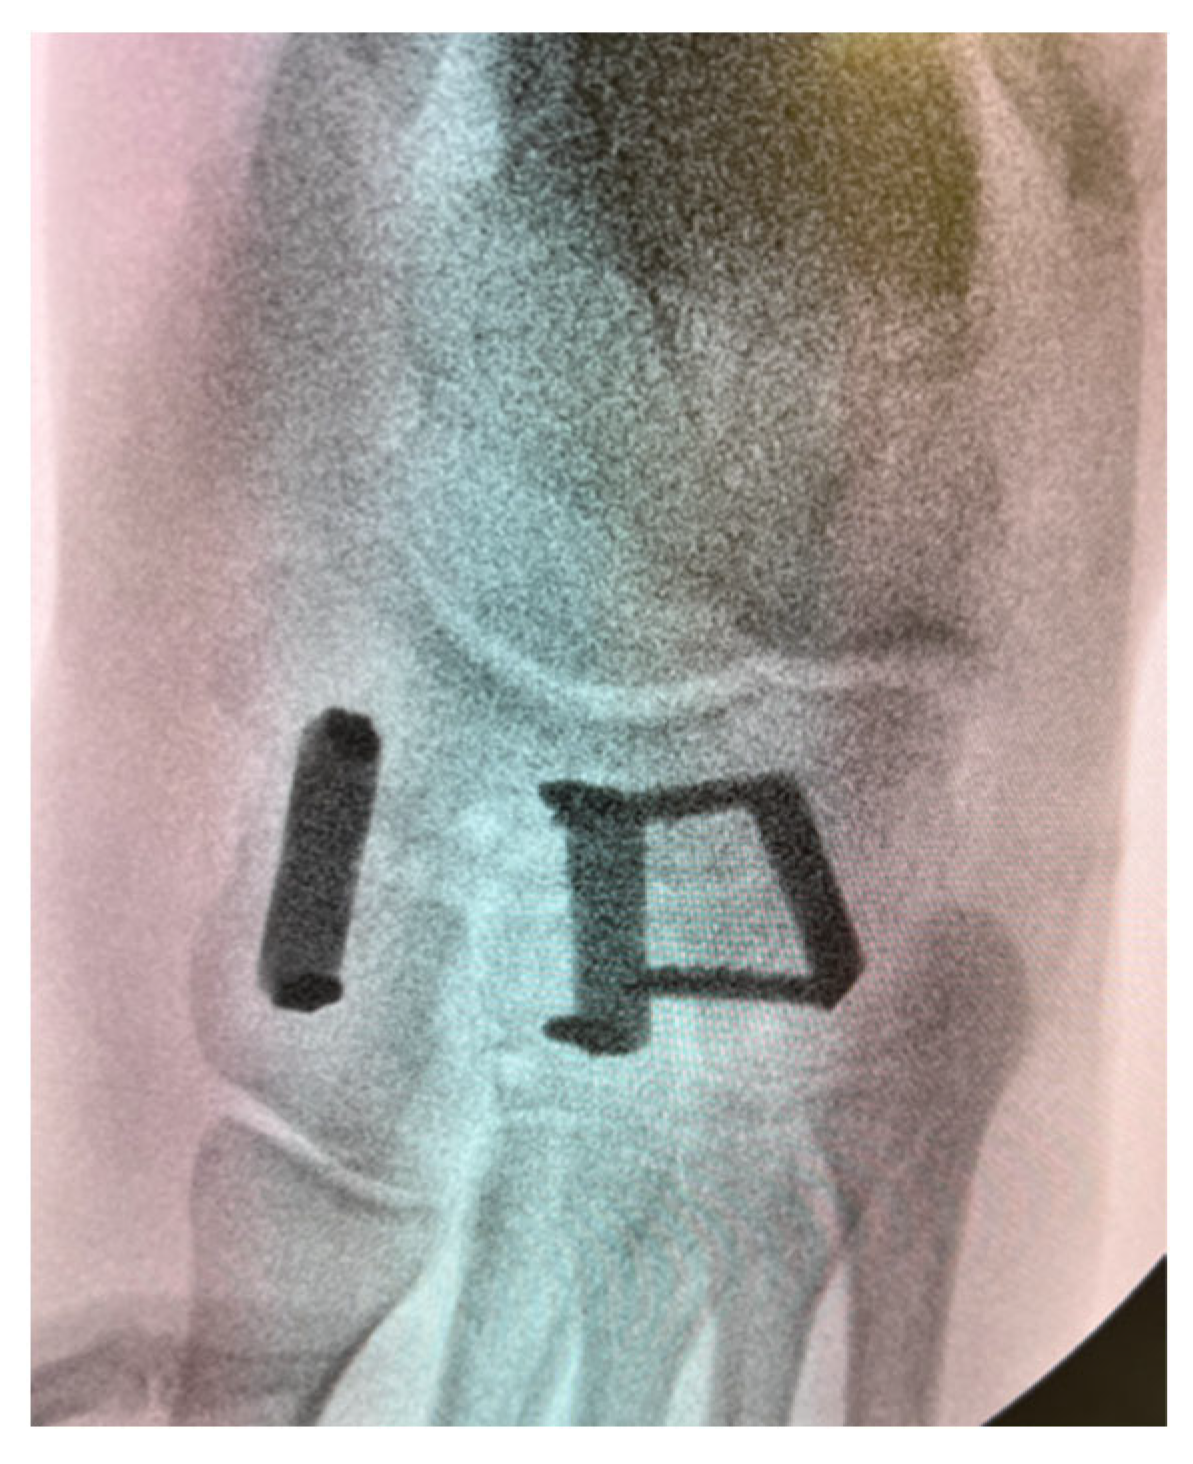

Figure 6. Intra-operative anteroposterior radiograph depicting a naviculocuneiform joint fusion with CCI fixation.